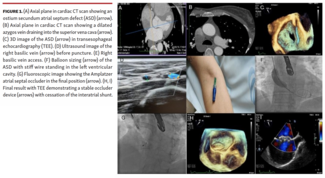

The authors report a case of a 55-year-old woman with an ostium secundum ASD with a significant left-to-right shunt at rest.

The authors report a case of a...